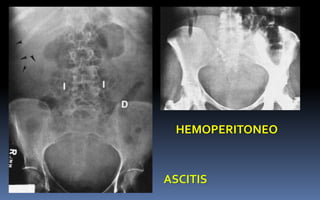

ASCITIS

HEMOPERITONEO